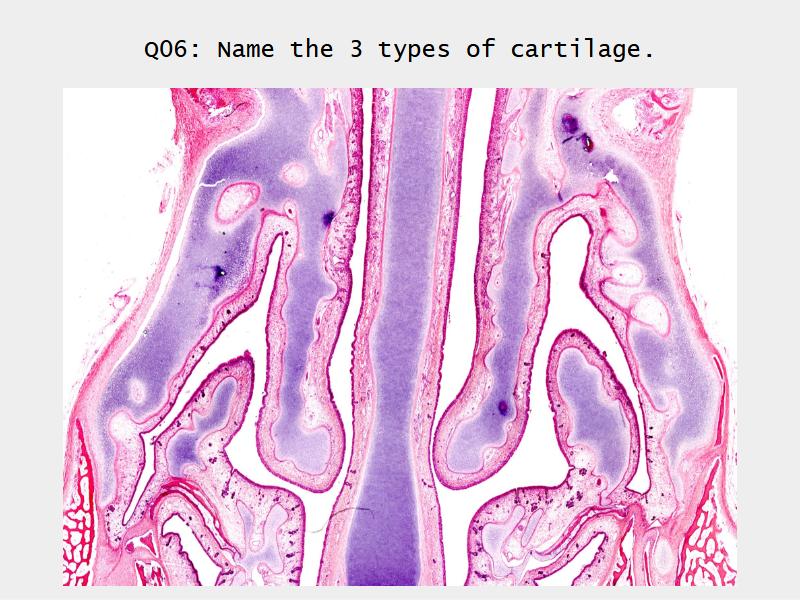

Slides: Respiratory System

- Slide 71: Nostril

Nostril